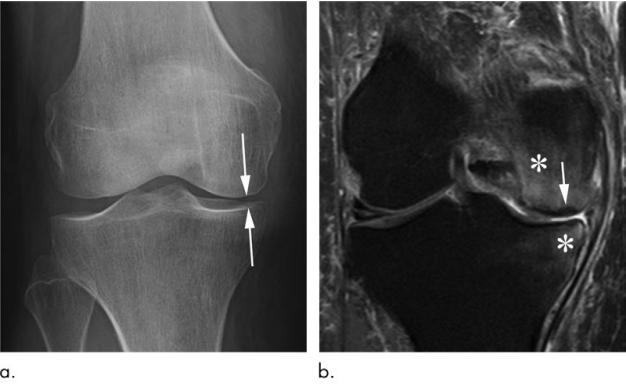

先和大家分享一个病例:这是一位69岁女性的膝关节软骨下不全性骨折,其表现为膝关节疼痛急剧恶化,无外伤病史。

图片a右膝正位片显示关节间隙内侧室变窄(箭头所示),无骨赘。没有骨坏死或软骨下不全骨折的迹象。

图片b与a同时应用冠状中等重量脂肪抑制MRI显示股骨内侧髁软骨下不全骨折,关节面无塌陷(箭头)。此外,还有明显的股骨和胫骨骨髓水肿(*)。

值得注意的是这名患者没有接受保守治疗(即,非负重活动),而直接的关节内注射皮质类固醇(激素)。